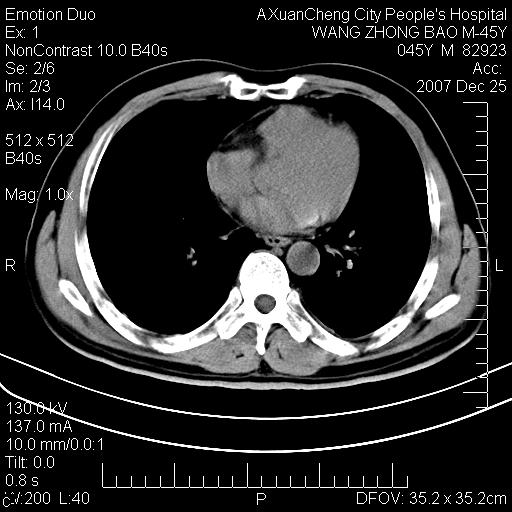

以下是引用qiuleiyu在2007-12-25 18:14:00的发言:[br]胰腺增大,周边渗出改变,肾前筋膜明显增厚,示少量积液.胆囊壁毛糙,周边少许渗出,胆总管壁厚,异常强化,然扩张不明显.结合病程急短;考虑;胆管炎,胆囊炎,胆源性胰腺炎可能大,请结合实验室检查及随访.

以下是引用lisihao在2007-12-25 14:23:00的发言:[br]急性水肿型胰腺炎[br]依据:1、胰腺弥漫性肿大,边缘稍毛糙;[br] 2、双侧肾周筋膜增厚,尤以左侧为甚(重要征象)[br] 3、双侧后胸膜增厚(刺激性炎症);[br] 4、结合病史,查血尿淀粉酶应该可以确诊。